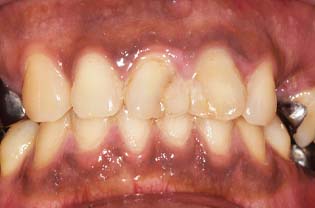

オールセラミック、

の症例

※ 横にスクロールできます

| 年齢・性別 | 41歳・男性 |

|---|---|

| 治療期間 | 3ヶ月 |

| 治療内容 | オールセラミック・ ジルコニアボンド |

| 治療本数 | 17本 |

| 治療費用 | オールセラミック(110,000円(税込)×12本) +ジルコニアボンド(165,000円(税込)×5本) |

| 副作用等 | かみ合わせがとても強い方の場合、 稀に割れてしまうことがあります。 |